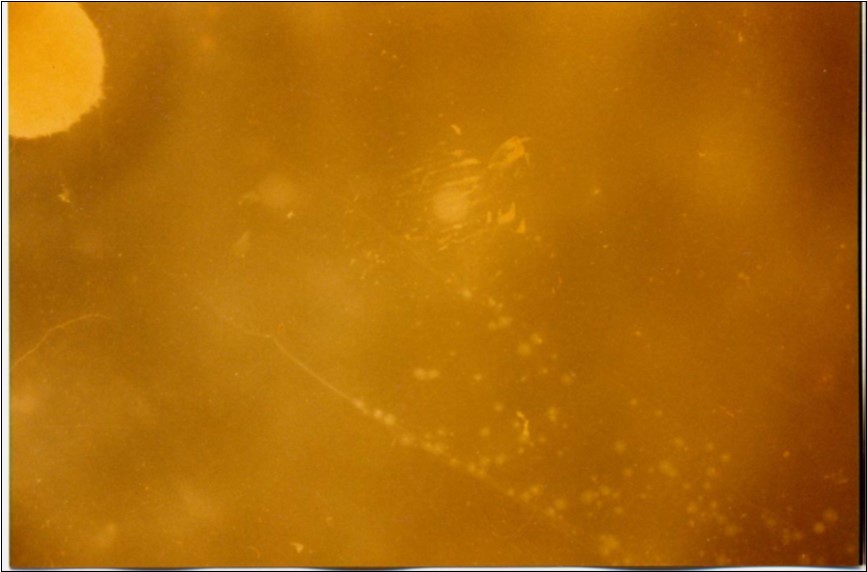

No mycoplasma was isolated from slaughterhouse samples. Three mycoplasma isolates were recovered from three out of six cases showing typical clinical signs and P.M. lesions. The isolates were identified as Mmm depending on cultural characteristics (Figure 1), digiton in test (Figure 2), and growth inhibition test.

Figure 1.Colonial morphology of Mmm of recent field isolate grown on heart infusion agar after 3 days of incubation (×40).

Colonial morphology of Mmm of recent field isolate grown on heart infusion agar after 3 days of incubation (×40).